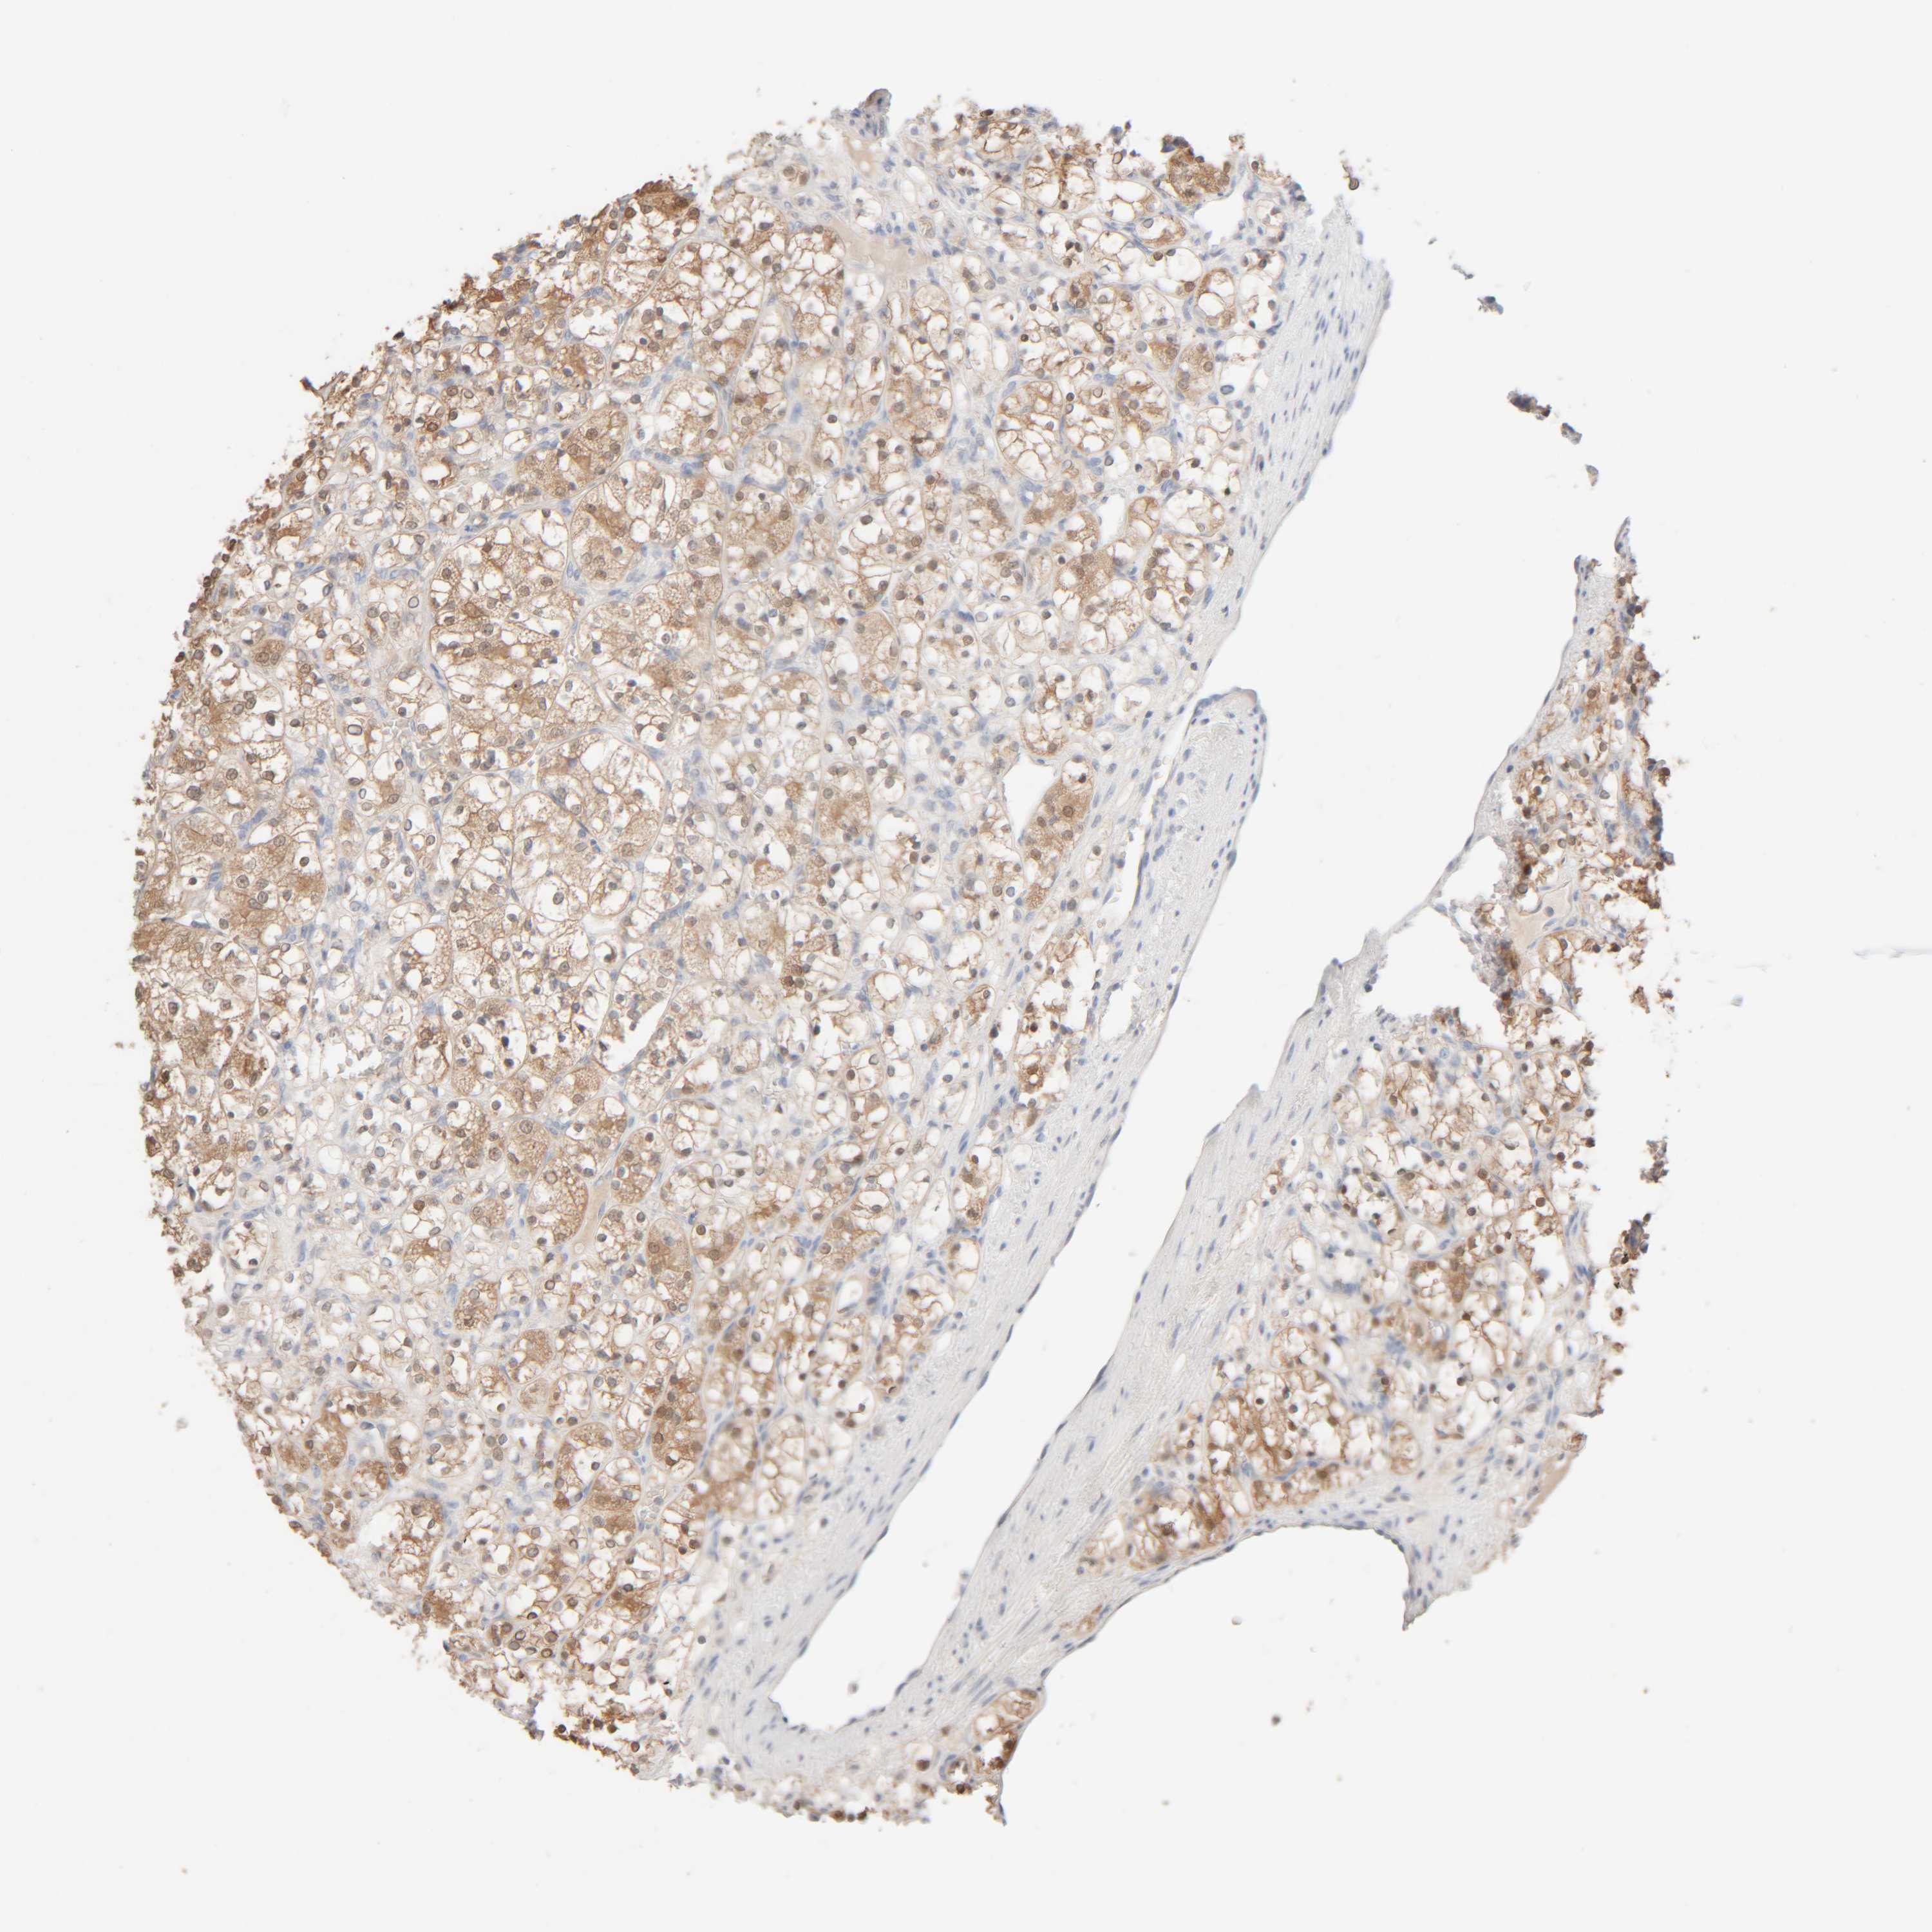

KIDNEY RENAL CLEAR CELL CARCINOMA (VALIDATION) - Interactive survival scatter ploti

The Survival Scatter plot shows the clinical status (i.e. dead or alive) for all individuals in the patient cohort, based on the same data that underlies the corresponding Kaplan-Meier plots. Patients that are alive at last time for follow-up are shown in blue and patients who have died during the study are shown in red.

The x-axis shows the expression levels (FPKM) of the investigated gene in the tumor tissue at the time of diagnosis. The y-axis shows the follow-up time after diagnosis (years). Both axes are complimented with kernel density curves demonstrating the data density over the axes. The top density plot shows the expression levels (FPKM) distribution among dead (red) and alive patients (blue). The right density plot shows the data density of the survived years of dead patients with high and low expression levels respectively, stratified using the cutoff indicated by the vertical dashed line through the Survival Scatter plot. This cutoff is automatically defined based on the FPKM cutoff that minimizes the p-score. The cutoff can be changed by dragging the vertical line or by entering a cutoff value in the square labeled "Current cut-off".

Under the Survival Scatter plot the p-score landscape (black curve; left axis) is shown together with dead median separation (red curve; right axis). Dead median separation is the difference in median mRNA expression between patients who have died with high and low expression, respectively. It is calculated as follows: median FPKM expression of dead patients with high expression - median FPKM expression of dead patients with low expression. This is intended to aid the user in visually exploring custom cutoffs and the associated p-scores and dead median separation.

Individual patient data is displayed and can be filtered by clicking on one or more of the category buttons on the top of the page. Categories describing expression level and patient information include: high, low, alive, dead, female, male and tumor stages. The scale of the x-axis can be toggled between linear and log-scale by clicking on the "x log" button. Mouse-over function shows TCGA ID, patient information and mRNA expression (FPKM) for each patient.

& Survival analysisi

Kaplan-Meier plots summarize results from analysis of correlation between mRNA expression level and patient survival. Patients were divided based on level of expression into one of the two groups "low" (under cut off) or "high" (over cut off). X-axis shows time for survival (years) and y-axis shows the probability of survival, where 1.0 corresponds to 100 percent.

RIDA is not prognostic in Kidney Renal Clear Cell Carcinoma (validation)

: 121.29

Average pTPM 152.5

Number of samples 100